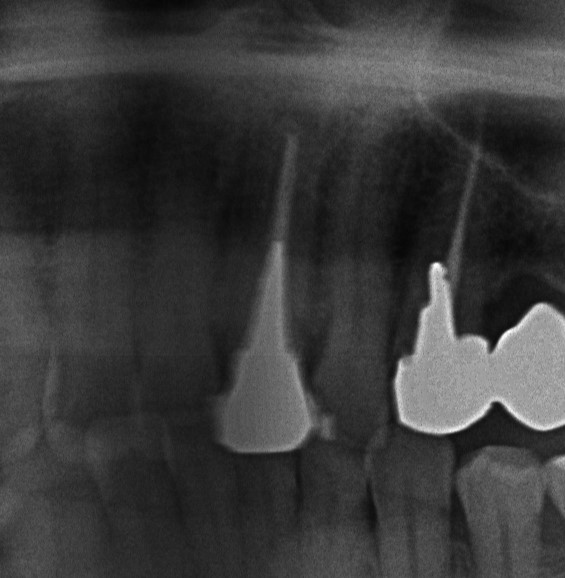

今回は左上の一番前の歯の根っこの治療になります。前の歯医者さんで断られただけあって土台も深くとるの大変そうです。

まずはかぶせものを外して土台だけの状態にしてその後土台をとっていっています。

土台をとると中が真っ黒ここから感染して症状を出していたのでしょうね。

今後は根っこの治療をしていき症状が落ち着いたの確認をして最終的なお薬を入れていく予定です。